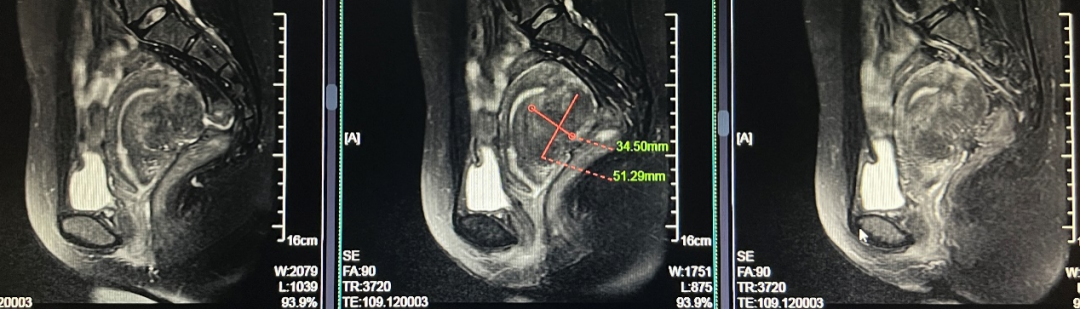

患者女,28岁,2021-06-07于青岛市妇女儿童医院就诊。 主诉:进行性痛经加重3年余。 现病史:患者月经初潮即有经期下腹痛,无需口服止痛药物。3年前痛经渐进性加重,目前经期腹痛VAS评分8分,伴恶心呕吐、肛周坠胀感。伴有非经期腹痛,VAS评分4分,持续4-5天,有深部性交痛。月经周期、经期及经量较前无明显改变。我院就诊超声提示:子宫后壁探及低回声结节,大小46mm*56mm*42mm,考虑子宫肌瘤。患者有明确生育要求,为求进一步治疗,门诊以“子宫腺肌病?子宫肌瘤?”收入院。患者自发病以来,神志清,精神可,饮食正常,经期夜间睡眠欠佳,体重较前无明显增减。 既往史:体健,否认慢性病及传染性疾病病史,否认外伤史,否认输血史,否认食物、药物过敏史。 月经及婚育史:既往月经规律,周期28-30天,经期5-6天,末次月经:2021-05-24。G1P0A1,2021年4月孕11周“稽留流产”行药物流产1次。 家族史:无特殊。 体格检查:T36.2℃,P77次/分,R18次/分,BP101/67mmHg,身高160cm,体重56kg。疼痛评分:0分。心、肺、腹部查体无异常。 专科查体: 妇科查体:外阴发育正常,阴道畅,宫颈光滑,子宫后位,增大如孕2月,固定、活动差,无压痛,双侧附件区未及异常。三合诊:左侧骶韧带触及触痛结节。 辅助检查: 2021-06-03 B超:子宫后位,宫体大小正常,形态规则,肌层内回声欠均匀,后壁肌层探及低回声结节,大小约46mm*56mm*42mm,边界清。宫腔内膜受压前移,厚10.1mm。宫颈形态正常。左侧卵巢探及液性暗区,大小约39mm*29mm,透声好,右侧卵巢大小正常。右侧附件区未见明显异常。 2021-06-07 肿瘤指标:糖类抗原CA19-9 52.21U/ml;糖类抗原CA125 112.9U/ml ↑; 2021-06-07 MRI提示:子宫后壁子宫腺肌病、盆腔子宫内膜异位症? 初步诊断: 2.盆腔子宫内膜异位症 3.不良孕产史 1.2021-06-08在镇静镇痛下行聚焦超声消融手术(FUAS)治疗。术后增强核磁检查提示子宫后壁腺肌病灶内无灌注区,子宫内膜及浆膜血流灌注正常。 2.2021-06-22术后第一次月经来潮,痛经较前减轻,VAS评分2-3分。术后辅助GnRh-a治疗3周期辅助治疗,同时口服钙片补钙治疗,用药期间闭经,无腹痛等不适。 3.GnRh-a治疗3周期后,2021-09-08复查B超:子宫后位,宫体大小正常,形态规则,肌层内回声欠均匀,后壁肌层探及高回声团,大小约38mm*37mm*26mm,边界清,内见少许血流信号。宫腔内膜受压前移,厚4.1mm。宫颈形态正常。双侧卵巢大小正常。双侧附件区未见明显异常。 4.2021-11-22月经复潮,经量正常,痛经VAS 2分,月经第5天开始口服地屈孕酮20mg QD,每月经周期20天,建议试孕半年。 5.2022-04-27随访复查,LMP:2022-02-24,停经9周,B超:子宫后位,体积增大,形态饱满,被膜光滑,后壁肌层回声不均匀,内见低回声区,较大范围约35mm*26mm,宫腔内见大小约32mm*31mm*24mm妊娠囊,张力可,内见胎芽,纵径22.4mm,心管搏动规律,妊娠囊下方探及不规则液性暗区,范围约21mm*8mm。双侧附件区未见明显异常。继续口服地屈孕酮10mg q8h保胎治疗。孕期进展顺利,2022-11-25外院足月剖宫产1女婴,体重3300g,Apgar评分10分-10分。 子宫内膜异位症和子宫腺肌病是妇科常见疾病。除了引起疼痛和月经改变,越来越多的证据表明,这两种疾病对女性的生殖功能有重要影响。临床可表现为不孕不育和流产等,尤其是早期流产[1]。 本例患者B超提示“子宫肌瘤”可能,但后续评估更符合子宫腺肌病。弥漫性子宫腺肌病的超声检查准确性较高,但子宫腺肌瘤超声表现与子宫肌瘤相似,临床诊断需要结合患者的症状、CA125水平综合判断。相比超声,磁共振检查对子宫腺肌病的分型更有优势,也更容易发现合并的盆腔子宫内膜异位症。后位子宫的后壁腺肌病灶往往合并子宫直肠陷凹的内异病灶,本例患者即属于该情况,治疗策略应兼顾两种疾病并同时考虑患者的生育需求。 针对子宫腺肌病,传统的病灶切除手术对子宫损伤较大,合并盆腔子宫内膜异位症时,手术操作也较困难,所以对于有生育需求的患者选择手术治疗需要相当慎重。聚焦超声消融术(HIFU)可选择性消融子宫腺肌病病灶、使病灶缩小,同时保护子宫完整性,从而达到减轻症状、缩小病灶、改善生育的目的[2]。但无法同时消融盆腔子宫内膜异位病灶,需要联合药物综合治疗。 子宫腺肌病和子宫内膜异位症的慢病管理理念已逐渐被认可,药物治疗是基石。而目前一线用药促性腺激素释放激素激动剂、地诺孕素等均会抑制排卵,有生育需求的患者备孕时需要停药。而停药后的试孕期病灶复发和进展风险较高,从而影响妊娠几率。地屈孕酮10-20mg/d可缓解内异症痛经,不抑制排卵,兼顾子宫腺肌病和盆腔子宫内膜异位症患者的治疗和备孕。此外,对于疑有黄体功能不足者黄体期使用地屈孕酮还可能提高自然受孕率,备孕期周期性用药副作用低,安全性高。 子宫腺肌病不仅可导致患者的生育力低下,诸如排卵障碍、不孕、流产、早产、死产、胎儿生长受限等,还可导致妊娠期母亲并发症如剖宫产率增加、子痫前期、前置胎盘及胎盘早剥等[3],一旦妊娠应更加积极的给予保胎治疗和严密随访,积极补充孕酮以抑制子宫平滑肌收缩,尽可能提高活产率。 子宫腺肌病和子宫内膜异位症具有类似的发病机制,也常常合并存在,严重影响女性的生殖健康。针对两种疾病的治疗应规范化、个体化、微创化。给予规范用药或手术治疗,减灭和消除病灶,减轻临床症状的同时,应充分考虑患者的主要诉求、年龄和生育需求,尽可能选取创伤小的治疗方式。重视患者全生命周期的管理,早诊早治、促进生育、长期管理预防复发,避免反复手术带来的创伤,定期随访,警惕恶变。 该患者28岁,痛经伴非经期腹痛,临床诊断符合子宫腺肌瘤合并子宫内膜异位症。既往不良孕产史,有明确生育需求,具有治疗指征。针对后壁子宫腺肌瘤传统手术方式对子宫损伤较大不利于患者后续妊娠,康医生选择了聚焦超声消融术治疗缩小子宫腺肌病病灶,减轻患者痛经并改善子宫形态,有利于提高妊娠几率。 子宫腺肌病和子宫内膜异位症在年轻患者中复发几率极高,可谓“不死的癌症”,当患者又有生育需求时,如何兼顾治疗和生育确实给我们提出了较高的要求。该患者在停用GnRh-a后月经来潮,备孕期间给予口服地屈孕酮稳定病灶、改善痛经,同时不会影响下丘脑-垂体-卵巢轴(HPO轴)而抑制排卵,还能提高自然受孕几率,可谓一举两得。 患者服用地屈孕酮3个月后便顺利妊娠,体现了治疗的有效性。更难能可贵的是,康医生重视子宫腺肌病患者的孕期管理,妊娠后继续给予口服地屈孕酮积极保胎,抑制子宫平滑肌收缩,也体现了将子宫腺肌病患者作为高危孕产妇管理的治疗理念。 参考文献: